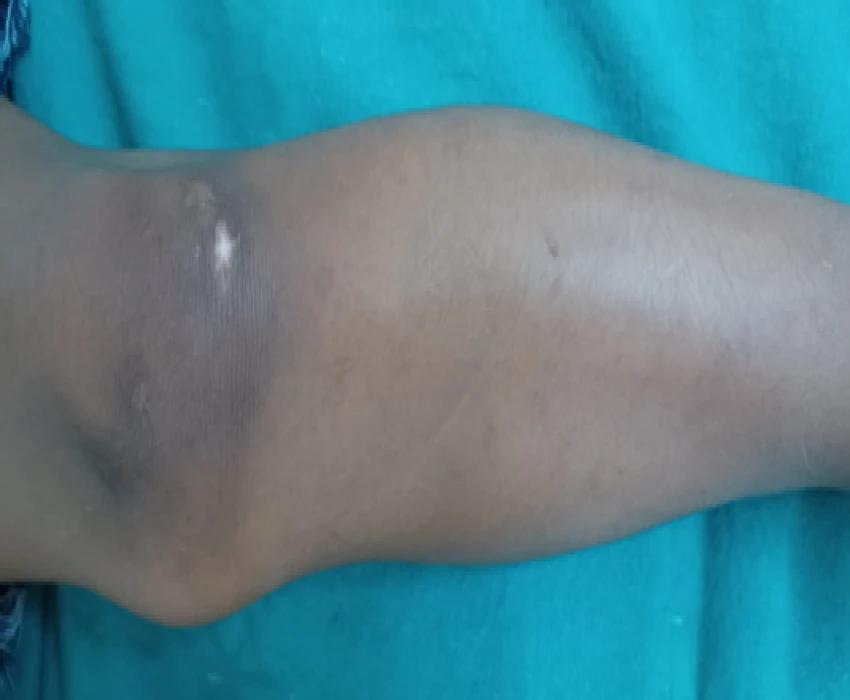

Hypohidrotic ectodermal dysplasia (HED) is characterized by hypotrichosis (sparseness of scalp and body hair), hypohidrosis (reduced ability to sweat), and hypodontia (congenital absence of teeth).The cardinal features of classic HED become obvious during childhood.Physical growth and psychomotor development are otherwise within normal limits.